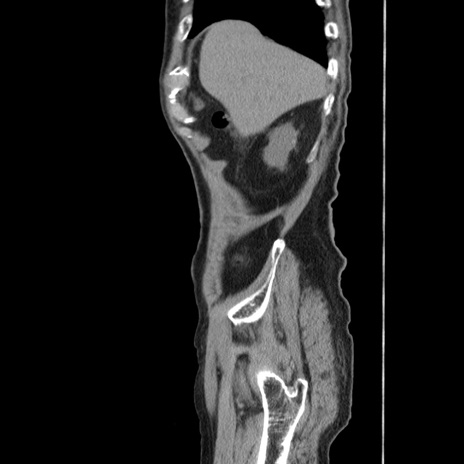

症例24(矢状断像)

【症例】80歳代男性

【主訴】左側腹部痛、嘔吐

【現病歴】本日早朝より左腹部に痛みあり。昼頃嘔吐認めたため、救急要請。

【既往歴】直腸癌(Mile手術)、胆摘

【身体所見】意識清明、BT 35.9℃、BP 221/93mmHg、SpO2 97%(RA) 、腹部:左ストーマ周囲に限局性の腹部膨隆あり。 膨隆部自発痛・圧痛あり・軟。

【データ】WBC 7700、CRP 0.09